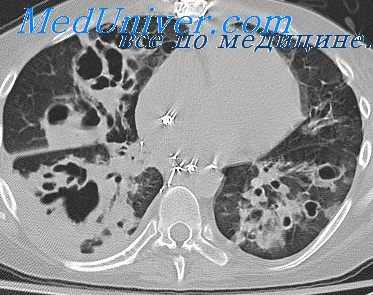

Картина, выявляемая по данным рентгенографии легких, различается в зависимости от формы бактериальной деструкции легких. В типичных случаях легочные деструкции определяются в виде полостей с горизонтальным уровнем жидкости, вокруг которых распространяется воспалительная инфильтрация легочной ткани. При плевральных осложнениях выявляется смещение тени средостения в здоровую сторону, уровень жидкости в плевральной полости, частичный или полный коллапс легкого. В этом случае целесообразно дополнение рентгенологической картины данными УЗИ плевральной полости, плевральной пункции и исследования экссудата. Бактериальную деструкцию легких требуется дифференцировать от полостной формы рака легкого, бронхогенных и эхинококковых кист, кавернозного туберкулеза. В проведении дифдиагностики, должны участвовать пульмонологи, торакальные хирурги, фтизиатры.